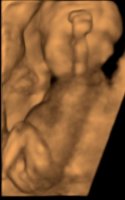

Vi har heldigvis muligheten til og dra tilbake om 2 uker så veldig spennende og se da. Her ser du bildet fra i går. Fikk ikke noe på ordinær av det området

På 3d ultralyden i går sjekket hun flere ganger. Og så det samme som på bildet her. Men tror jeg var så sjokkert at jeg ikke fikk med meg noe som helst.

På 3d ultralyden i går sjekket hun flere ganger. Og så det samme som på bildet her. Men tror jeg var så sjokkert at jeg ikke fikk med meg noe som helst. Ser jo ut som en gutt her. Og er mest sannsynlig det. Bare redd for og stole på det nå. Fryktelig dårlig på og håndtere overraskelser

Ser jo ut som en gutt her. Og er mest sannsynlig det. Bare redd for og stole på det nå. Fryktelig dårlig på og håndtere overraskelser

Vi har heldigvis muligheten til og dra tilbake om 2 uker så veldig spennende og se da. Her ser du bildet fra i går. Fikk ikke noe på ordinær av det områdetPå 3d ultralyden i går sjekket hun flere ganger. Og så det samme som på bildet her. Men tror jeg var så sjokkert at jeg ikke fikk med meg noe som helst.

Ser jo ut som en gutt her. Og er mest sannsynlig det. Bare redd for og stole på det nå. Fryktelig dårlig på og håndtere overraskelser

På bildet ditt ser det ut som en gutt

Oi, det var jo litt rart, for på bildet fra 3D ser det jo ut som en gutt